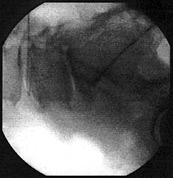

Auch andere schwerwiegende Komplikationen – Entzündungen etwa – treten äußerst selten auf. Allerdings erfordert das Legen der Sonde ein hohes Maß an Präzision. Daher wird die gesamte Operation ständig am Röntgenschirm beobachtet.